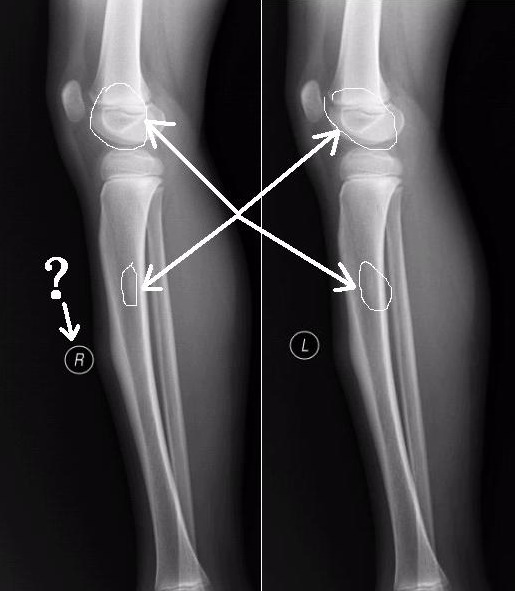

左胫骨中段前缘局限性骨皮质增厚,其内隐约见一低密度影,考虑骨样骨瘤可能,局限性骨皮质增厚可能,建议ct进一步检查。最后一张片子应该是l吧。

左胫骨前缘骨皮质增厚,有向前凸起改变,与之比较右侧胫骨皮质均匀光整。支持二楼的意见。从骨性标记看,小腿的左右标注楼主有误。

左胫骨中段前缘局限性骨皮质增厚。